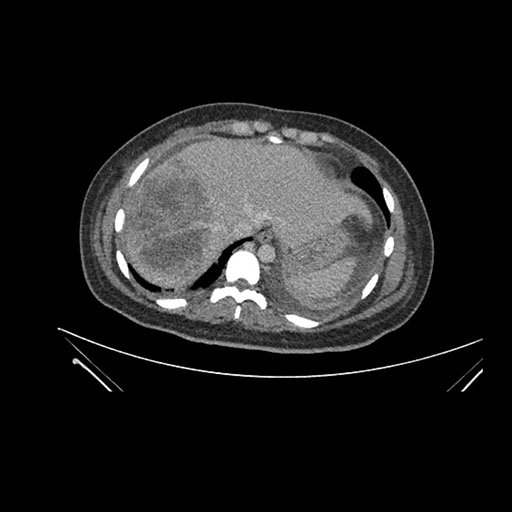

Imaging Analysis

Look through the patient's CT scan to identify any areas of concern for the necessary procedure.

Axial Arterial

Based on initial findings, which issue(s) would you be most concerned about?